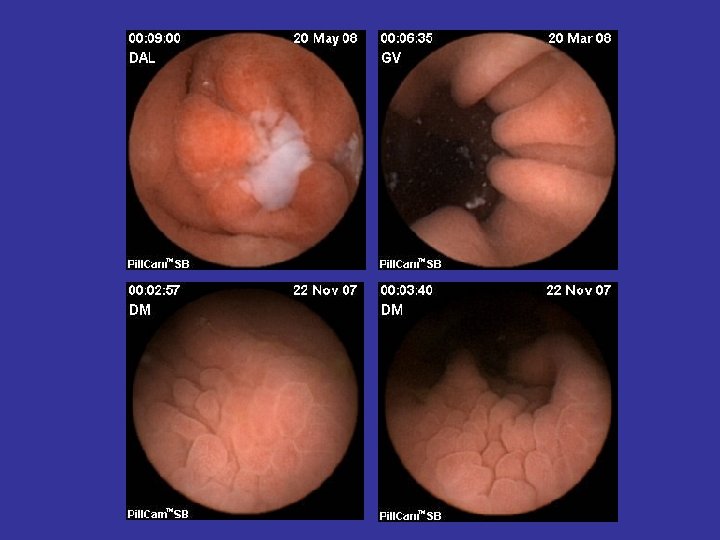

Tipuri de leziuni depistate in BC • • Eroziuni Edem mucosal Congestie parcelara Ulceratii aftoide; Ulcere liniare/ neregulate/ confluente; Pseudopolipi inflamatori; Stenoze inflamatorii;

Boala celiaca • Indicatiile WCE – Boala celiaca refractara la DFG pt vizualizarea si stabilirea extensiei atrofiei vilozitare – Suspiciunea de complicatii (ADK, limfom, enterita ulcerativa)

Tumorile intestinului subtire • Maligne (60%) – Adenocarcinoame – Limfoame – Tumori carcinoide – Metastaze (melanom) – Sarcoame • Benigne (40%) – Tumori stromale (GIST) – Adenoame – Hamartoame – Hemangioame